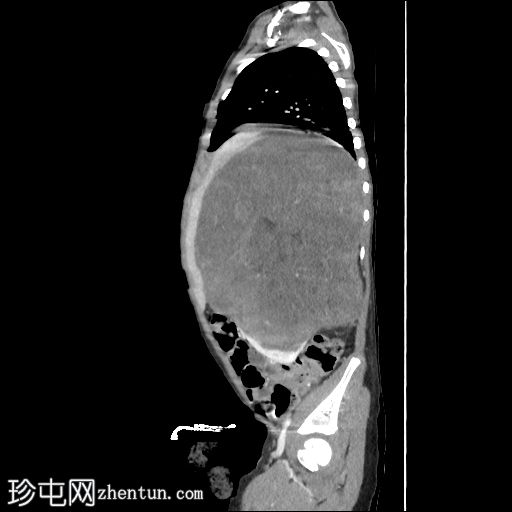

轴位增强扫描(门静脉期)

右肾向下移位至中线,呈水平位。肾上极可见一大小不一、边界相对清晰的肿块。未见明显钙化或坏死。肿块延伸至中线,但未越过主动脉/中线左侧。下腔静脉上段向前左侧移位。尽管移位,右肾静脉和动脉外观正常,未见狭窄/扩张或明显的肾静脉血栓形成。

结肠和小肠袢,尤其是在右侧腹部,向下移位,但外观无明显异常。

未见腹膜后淋巴结肿大。骨骼结构外观正常,无明显的溶骨性或成骨性改变。